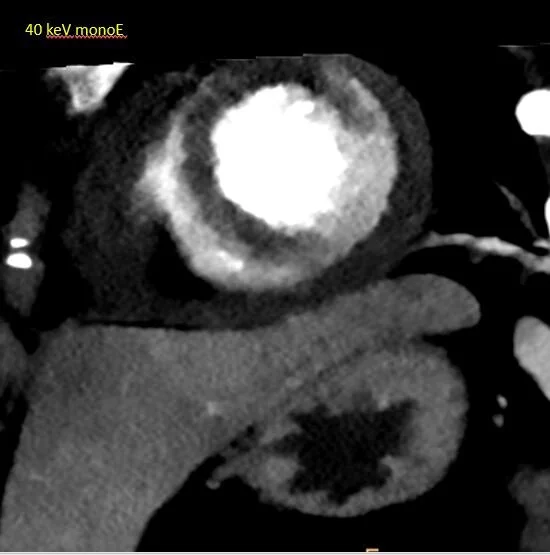

The next day she had abdominal pain and a CT scan of the abdomen and pelvis was performed. There was no acute finding in the abdomen, but the cuts through the lower chest showed interesting findings in the LV. On 40 keV monoE and iodine map, there is a large perfusion defect in the LV corresponding to the LAD territory. This is better seen on short-axis view. On spectral CT, this is a slam dunk, while on routine CT it would be quite a stretch to make this call.

40 keV monoE: Impossible to miss